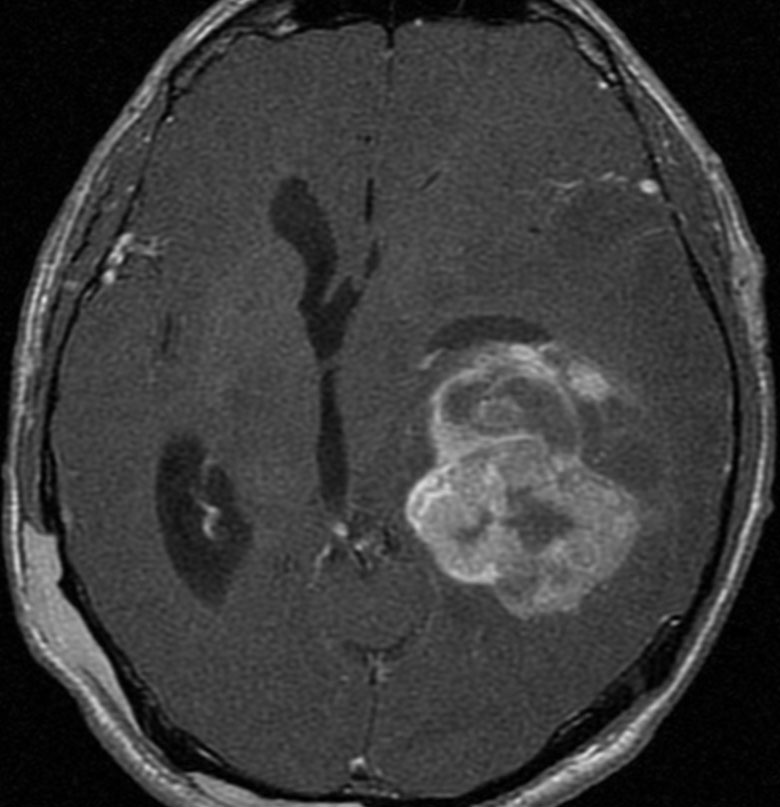

12歳時,私のところへ来た時のガドリニウム増強像です。開頭手術で扁桃体を含めて全摘出してから発作は止まり,術後3年で抗てんかん薬は中断できています。